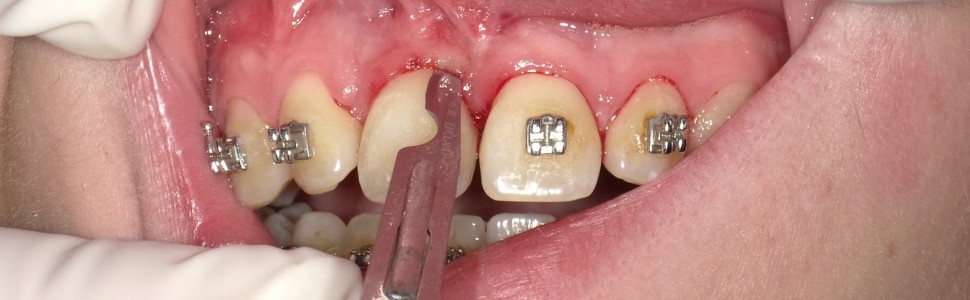

W artykule przedstawiono dwuetapową korektę tkanek miękkich, w pierwszej fazie o charakterze resekcyjnym, w drugiej zwiększającą objętość tkanek miękkich w kompleksowym chirurgiczno-ortodontycznym leczeniu zatrzymanego zęba siecznego przyśrodkowego.

Wprowadzenie procedur z zakresu chirurgii śluzówkowo-dziąsłowej pozwoliło nie tylko wprowadzić ząb do łuku, ale również uzyskać zadowalający efekt estetyczny.

The article presents a two-stage soft tissue correction, resective, and then increasing the volume of soft tissues in the comprehensive treatment of an impacted central incisor. The introduction of mucogingival procedures allowed the proper tooth insertion into the arch as well as to obtain a satisfactory aesthetic effect.